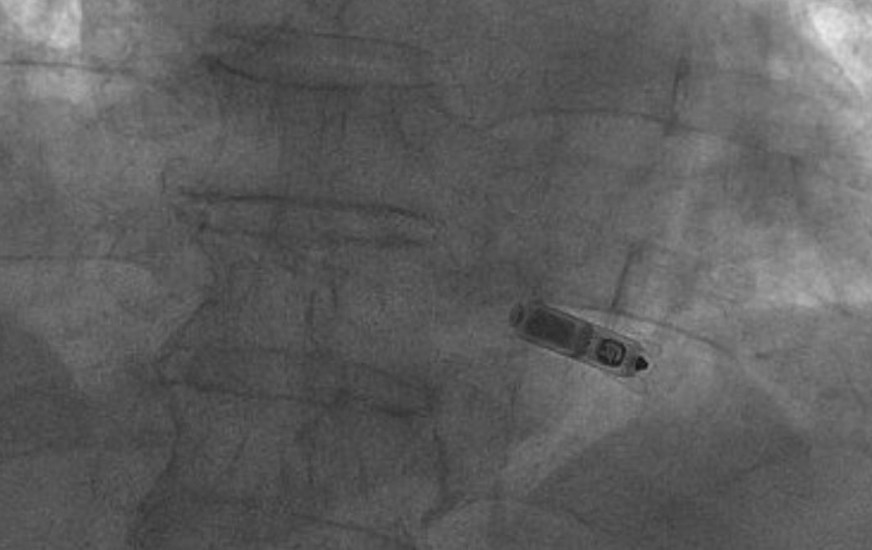

Các bác sĩ Chuyên khoa Tim Mạch, Bệnh viện FV quyết định đặt máy tạo nhịp tim không dây cho ông Nghĩa. Đây là một thiết bị chỉ nhỏ như viên thuốc con nhộng (bằng 1/10 máy tạo nhịp có dây), được đưa trực tiếp vào buồng tim của bệnh nhân mà không cần tới dây dẫn.

Theo đại diện bệnh viện FV, ca phẫu thuật kéo dài 30 phút. Bệnh nhân được gây tê, máy tạo nhịp được đưa vào buồng tim bằng một ống thông từ tĩnh mạch đùi. Bệnh nhân đã hồi phục nhanh vào ngày sau đó. Đối với máy tạo nhịp có dây, bệnh nhân cần tránh vận động trong thời gian mới cấy máy ít nhất 4 tuần để giảm nguy cơ chảy máu túi máy tạo nhịp. Trong khi đó, khi đặt máy tạo nhịp không dây thì ông Nghĩa có thể sinh hoạt và tự thực hiện các hoạt động cá nhân thường ngày. Lần tái khám gần đây, ông khỏe mạnh, các chỉ số nhịp tim đều đạt yêu cầu.